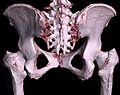

Jedes Pixel in einem Schnittbild entspricht einem Volumenelement (Voxel) des gesamten dreidimensionalen Datensatzes. Die Höhe des Voxels entspricht dabei der Schichtdicke. In der Nachbearbeitung lassen sich aus den Voxeln beispielsweise beliebig im Raum angeordnete Schichtbilder (multiplanare Rekonstruktion, MPR), geschichtete (Subvolumen-)Maximumintensitätsprojektionen (MIPs) oder dreidimensionale Bilder des untersuchten Objekts (Volumenrendering) errechnen.

-

3D-Rekonstruktion (Volumenrendering) aus einem Herz-CT-Datensatz -

3D-Rekonstruktion (Volumenrendering) des Beckens aus einem CT-Scan -

Rekonstruiertes 3D-Zahnmodel aus Daten eines DVT-Scans -

3D-Rekonstruktion (Volumenrendering) eines MRT-Datensatzes